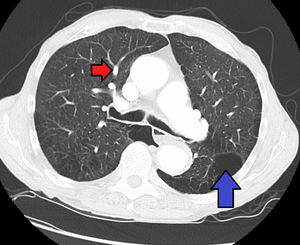

لأن فرط ضغط الدم الرئوي يتكون من خمس أنواع رئيسية -فرط ضغط الدم الرئوي الشرياني، الوريدي، الناتج عن قلة الأكسجين، الناتج عن الامراض التخثرية والانصمامية والناتج عن آليات متنوعة-؛ فانه يتم اجراء سلسلة من الاختبارات للتفريق بينها. يتم عمل اجراءات لاحقة للتأكد من وجود فرط ضغط الدم الرئوي واستثناء الامراض الاخرى, هذه الاجراءات تشمل: اختبار وظائف الرئة؛ تحليل الدم لاستبعاد امراض الايدز والكبد وأمراض المناعة الذاتية؛ مخطط كهربائية القلب؛ قياسات غازات الدم الشرياني؛ صورة أشعة سينية للصدر (متبوعة بصورة طبيقية عالية الوضوح اذا تم الشك بوجود امراض رئوية خِلاليّة)؛ واختبار التهوية/التدفق لاستبعاد فرط ضغط الدم نتيجة الامراض التخثرية والانصمامية المزمنة. لا يتم اخذ خزعة من الرئة الا اذا تم الشك بحدوث فرط ضغط الدم نتيجة لامراض رئوية خلالية؛ أيضاً، هناك تخوّفات ان خزعات الرئة قد تسبب نزيف نتيجة الضغط الرئوي البيني العالي. يتم أيضا قياس درجة التحسن طبيّاً عن طريق "اختبار السير لمدة 6 دقائق", بمعنى آخر، يتم حساب المسافة التي يستطيع ان يقطعها المريض خلال 6 دقائق. كلّما كانت نتائج هذا القياس ثابتة ومتحسنة فهي دليل على وجود فرص أفضل للنجاة.

من المطلوب وجود فرط في ضغط الدم الرئوي لتشخيص مرض فرط ضغط الدم الرئوي الشرياني. على الرغم من ان ضغط الشريان الرئوي يمكن تقديره بواسطة مخطط صدى القلب, لكن قياسات الضغط بواسطة قسطرة سوان-جانز من خلال الجانب الأيمن للقلب توفر الوسيلة الأفضل للقياس. ضغط الشريان الرئوي الانسدادي ومقاومة الاوعية الرئوية لا يمكن حسابها مباشرة من مخطط صدى القلب. لهذا فان تشخيص فرط ضغط الدم الرئوي الشرياني يتطلب قسطرة من الجانب الأيمن للقلب. قسطرة سوان-جانز تستطيع ايضا قياس مخرجات القلب، والتي تعتبر أكثر أهمية في حساب حِدّة المرض من قياس ضغط الشريان الرئوي. متوسط الضغط الشرياني الرئوي الطبيعي لشخص يعيش على مستوى سطح البحر يساوي تقريبا 8-20 مم زئبقي في حالة الراحة. فرط ضغط الدم الرئوي يحدث عندما يتجاوز الضغط الشرياني الرئوي 25 مم زئبقي في حالة الراحة.[13] لا يجب الخلط بين "متوسط الضغط الشرياني الرئوي" وبين "الضغط الشرياني الرئوي الانقباضي"، والذي يُسجل غالباً في بيانات مخطط صدى القلب. اذا كان الضغط الشرياني الرئوي الانقباضي يساوي 40 مم زئبقي فان متوسط الضغط الشرياني الرئوي يساوي 25 مم زئبقي. حِسابياً, فان متوسط الضغط الشرياني الرئوي =0.61 * الضغط الشرياني الرئوي الانقباضي + 2.